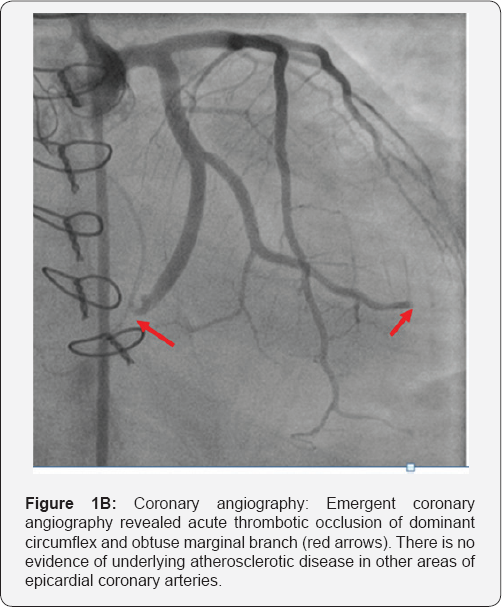

On hospitalization day 13, the patient suffered a pulseless electrical activity (PEA) arrest and was successfully resuscitated. Post-resuscitation 12-lead electrocardiogram (ECG) revealed inferior ST-segment elevations with reciprocal anterolateral ST-segment depressions (Figure 1A). Emergent bedside TTE revealed inferior and inferoseptal wall akinesis with estimated global LVEF of 10-15%. Emergent coronary angiography found that there was acute total occlusion in the mid segment of the large, dominant left circumflex artery with TIMI 0 flow (Figure 1B) considered as the culprit lesion for the STEMI. No significant atherosclerotic disease was apparent in other major epicardial coronary arteries. After wiring the lesion, aspirational thrombectomy using Priority One® aspirational catheter (Terumo Inventional Systems) was performed in the consideration of large thrombus burden without underlying atherosclerotic stenosis. Large amount of yellowish debris with minimal blood stain was retrieved after multiple passes (Figure 1C). Subsequent balloon angioplasty was also performed. No-reflow phenomenon persisted despite repeated efforts of aspiration, balloon angioplasty and intra-coronary adenosine administrations. Large burden of distal fungal emboli was thought to be the cause of no-reflow. Cultures of the aspiration contents from the circumflex artery were subsequently positive for Candida albicans, which was identical to previous blood culture growth. Non-selective aortic root angiography revealed evidence of aortic paravalvular abscess with communications between the aorta and pulmonary artery. Unsuccessful revascularization for embolic occlusion of large dominant circumflex led to pump failure and cardiogenic shock, as well as worsening of septic shock led to rapid clinical deterioration requiring increasing vasopressor support. Emergent surgical intervention was ultimately deferred citing prohibitively high risk for re-do aortic valve replacement in the setting of fungal endocarditis, paravalvular abscess, acute MI and mixed shock, to which the patient succumbed three days later.